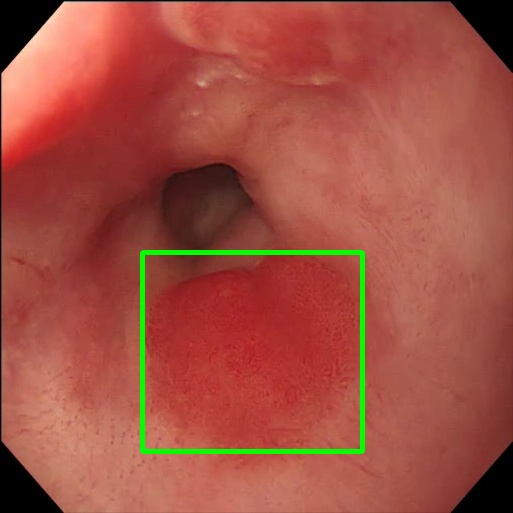

Gaussian Blur

Endoscopy GMAIMMbench Disease Diagnosis

Gaussian Blur - L0 (Original)

L0

L0 (Original)

Gaussian Blur - L1 (Moderate)

L1

L1 (Moderate)

Gaussian Blur - L2 (Severe)

L2

L2 (Severe)

Question

Focus on the square-highlighted area of this endoscopy image. What could be the potential diagnosis?

A barrett's esophagus B high-grade dysplasia C polyp D gastrointestinal tract cancer

Ground Truth: D. gastrointestinal tract cancer